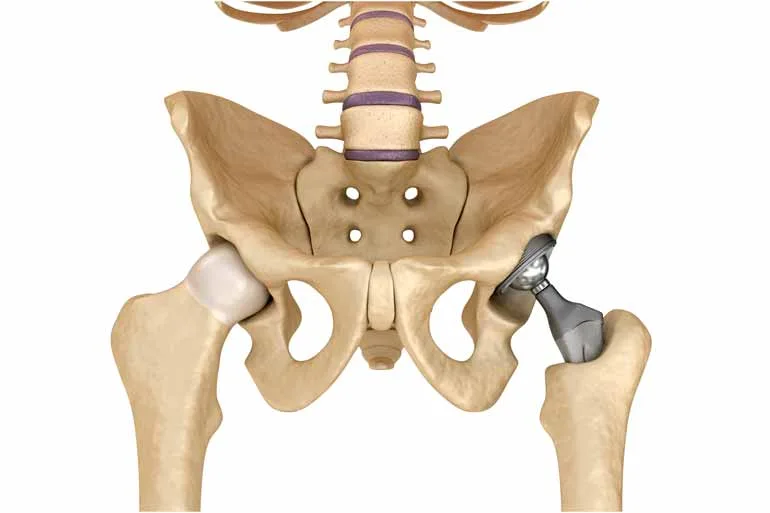

- Restaurando a mobilidade: Após a cirurgia, o paciente apresenta mobilidade limitada e amplitude de movimento reduzida. Os exercícios trabalhados na fisioterapia são destinados a restaurar o movimento articular do membro ou a área lesionada otimizando sua capacidade de movimento.